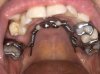

Letzten Freitag, 19.07.2024 hab ich nun den Slider, sowie die Brackets + Draht im UK eingesetzt bekommen. Die Spange im OK folgt noch, es nicht noch unklar welcher Zahn entfernt wird, da noch unsicher ist, ob der wurzelbehandelte Zahn den Druck des Sliders Stand hält - bisher alles gut :)

Hier noch zwei laienhaft erstellte Bilder direkt nach dem Einsetzten des Sliders und der Brackts im UK - OK folgt, da weiß ich noch nicht genau wann, das wird beim ersten Kontrolltermin am 13. August besprochen :)

image0.jpeg image1.jpeg